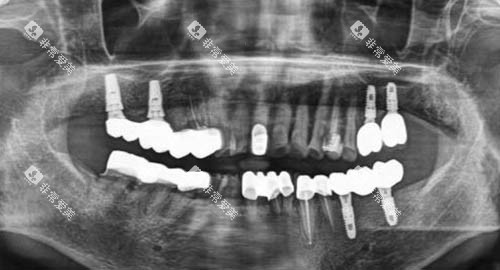

在种牙方面,医院引进了国内外可靠的种植系统,如瑞典诺贝尔种植系统、德国费亚丹种植系统等。

这些种植系统具有稳定性高、生物相容性好等特点,能够为患者提供更优质的种植体验。

医院的种植医生团队经验充足,他们经过严格的可靠培训,具备扎实的理论基础和丰富的临床经验。

在进行种植牙手术前,医生会运用可靠的口腔 CT 设备对患者的口腔状况进行齐全检查,制定个性化的种植方案。

例如,对于一些牙槽骨条件较差的患者,医生会采用骨增量技术,为种植体提供良好的支撑,提高种植可行性。